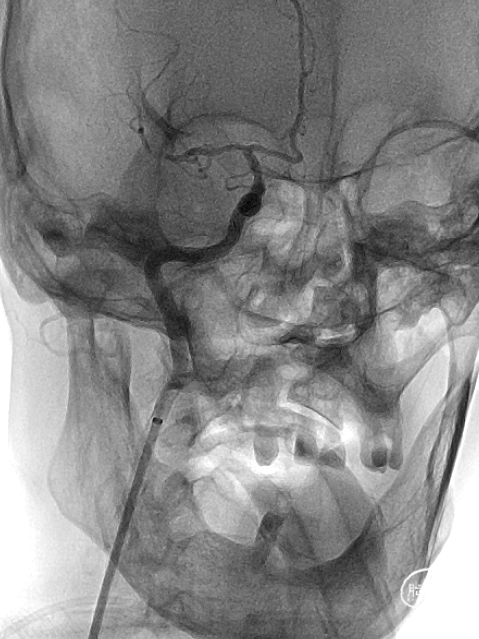

手术器械: